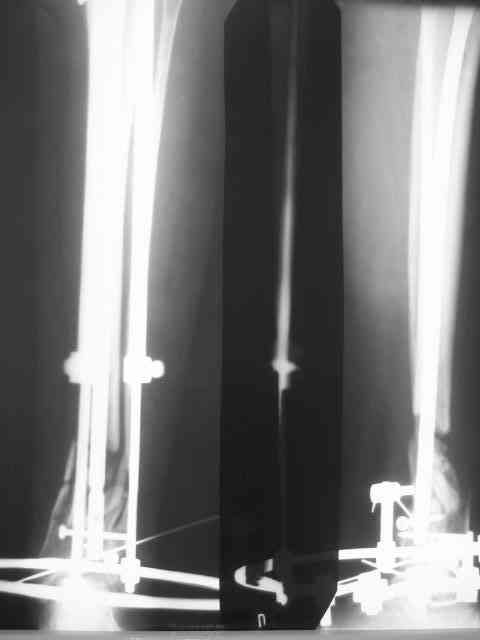

Здравствуйте коллеги! Вышел с отпуска и в палате оказалась данная

пациентка. Из истории выяснилось: травма 29.01.07 Диагноз: Открытый

оскольчатый перелом н/3 костей голени (якобы 2 Б Каплан), при

поступлении операция из трех букв и скелетное вытяжение + остальная

терапия. Затем выполнили остеосинтез штифтом (по ходу, Эксперт стоит)

видимо хотели  зацепится за дистальный отломок, но скорей всего все

было нестабильно и накинули этот  сокращенный АВФ. На сегодня (162

дня): Больная ходит с ограниченной нагрузкой на конечность  (трость).

Движения в г/стопе качательные. Трофика мягких тканей не

настораживает.  Воспаления м/тканей нет. В планах: 1. удаление штифта

2.Наложение стандартного АВФ с фиксацией стопы и устранение всех

смещений 3.Резекция нежизнеспособных костных отломков 4.Остеотомия в/3

большеберцовой кости с последующей дистракцией и замещением дефекта.